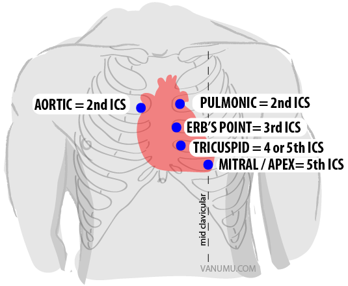

which space listed above can you use to hear the aortic and pulmonary valves?

how about if you wanted to listen to the mitral valve?

tricuspid valve?

right (aortic) and left 2nd ICS (pulmonic)

left 5th ICS

4th or 5th ICS